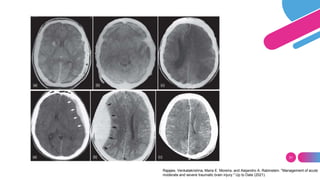

Rajajee, Venkatakrishna, Maria E. Moreira, and Alejandro A. Rabinstein. "Management of acute

moderate and severe traumatic brain injury." Up to Date (2021).

 HEMATOMAS SUBDURALES

 HEMATOMA EPIDURALES

 CONTUSIONES

 HEMATOMAS INTRACRANEALES

• Contusiones: 20 - 30%

• Lóbulo frontales y temporales

• En horas – días hematoma intracraneal

• Contusión coalescente con efecto de masa

• Ocurre en un 20% en TAC inicial.

• TAC A LAS 24 HRS POSTERIOR A LA

INICIAL.

H. Epidural H. Subdural

H. Subaracnoidea

H. Intraparenquimatosa

H. Ventricular